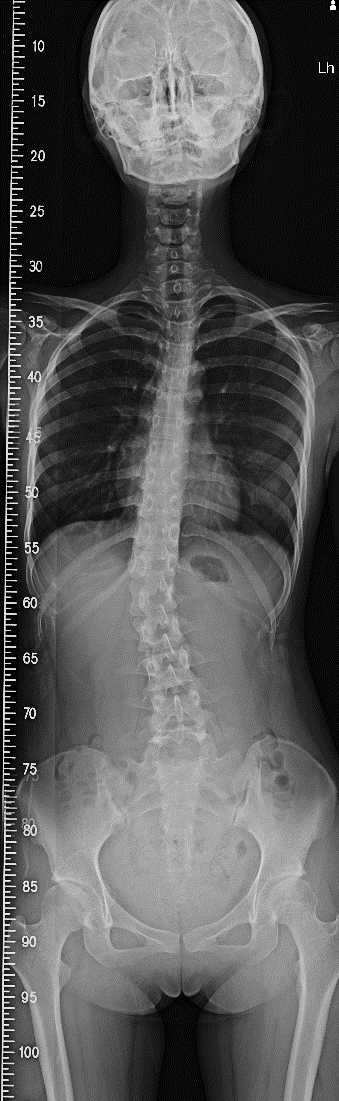

3. X光檢查如果以上檢查顯示出身體的不對稱,建議拍攝X光最能準確找出脊椎側彎

請注意一定要站立姿勢下拍攝,正面及側面各拍一張,以方便物理治療師做評估。